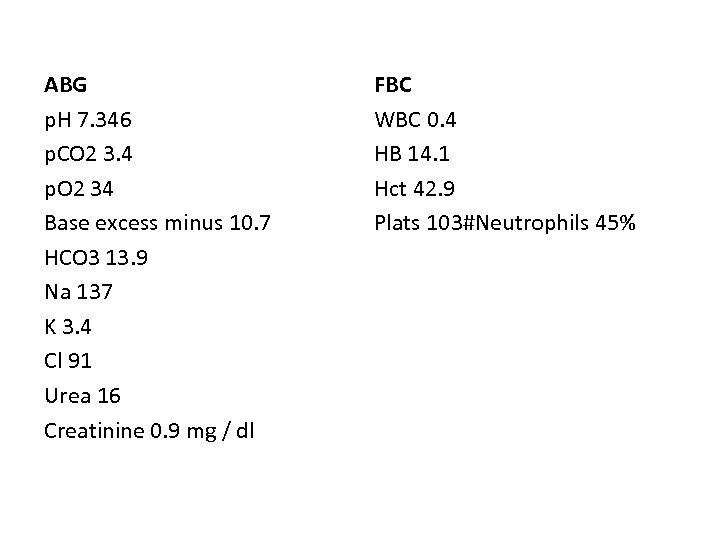

ABG p. H 7. 346 p. CO 2 3. 4 p. O 2 34 Base excess minus 10. 7 HCO 3 13. 9 Na 137 K 3. 4 Cl 91 Urea 16 Creatinine 0. 9 mg / dl FBC WBC 0. 4 HB 14. 1 Hct 42. 9 Plats 103#Neutrophils 45%

1. Having reviewed the blood results given, what is the most likely diagnosis and underlying cause? (1 mark) 2. Name 4 important management steps you would commence for this patient in the ED? (2 marks)

1. Having reviewed the blood results given, what is the most likely diagnosis and underlying cause? (1 mark) Neutropenic sepsis following chemotherapy 2. Name 2 important investigations and 2 treatments you would commence for this patient in the ED? (2 marks) Blood cultures (x 2) Chest x-ray Urine M/C/S Serum Lactate (assess for severe sepsis). CSF Clotting profile Broad spectrum IV antibiotics (accordingly to local policy) IV fluids discuss with haematology / oncology Consider commencing (white cell stimulating hormone) G(Neupogen 300 mcg daily subq for 5 days)